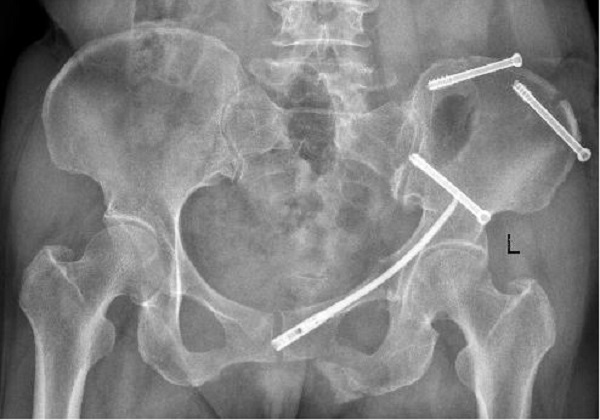

术前X线:

近日,二一五医院骨科医院创伤骨科收治了一例54岁女性骨盆骨折患者,查体发现左髋关节因疼痛活动受限,骨盆挤压分离试验(+),X线及CT检查提示骨盆骨折,骨盆骨折Young & Burgess 分型为LC—II型骨折,术前经左下肢骨牵引,手法协助闭合复位拍片可见骨盆骨折复位良好,郭永良主任医师详细了解患者受伤机制,根据复位效果及骨折类型制定了微创化手术治疗方案,即 LC-Ⅱ通道螺钉+耻骨髓内针的微创化治疗。